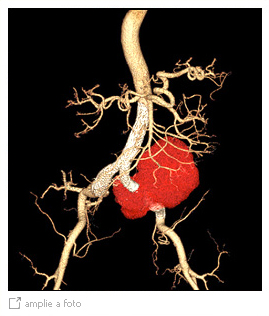

Aneurisma de ilíaca roto tratado com endoprótese